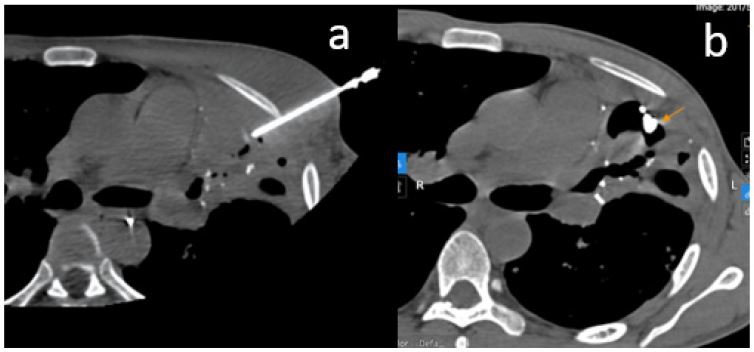

The patient initially underwent endovascular embolization. Selective angiography of the left internal mammary artery identified the pseudoaneurysm, which was embolized using NBCA glue mixed with lipiodol at a 1:4 ratio. Despite this, the patient continued to experience mild, intermittent hemoptysis. Follow-up CT imaging showed complete occlusion of the left bronchial artery and collateral branches from the left subclavian artery, but the pseudoaneurysm persisted with reduced contrast enhancement.

A second intervention was planned. Attempts to access the pseudoaneurysm via the pulmonary artery failed due to the small and peripheral feeding branch. Delayed-phase (7-second) angiography of the left subclavian artery revealed ongoing perfusion of the pseudoaneurysm through a lateral thoracic artery branch. An attempt at direct puncture under DSA guidance with an 18G needle was unsuccessful, and the patient experienced a 50 mL hemoptysis episode, which was managed locally. This confirmed that the pseudoaneurysm still had active blood flow.

Figure 2: (A) Pseudoaneurysm visualized on selective angiography of the left internal mammary artery, followed by selective embolization using glue. (B) Post-procedural image after the first intervention shows the pseudoaneurysm with reduced contrast enhancement compared to baseline.